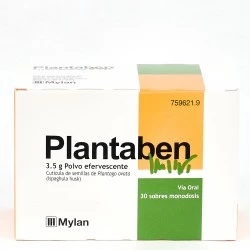

- Incrementadores del bolo: Plantago ovata En el intestino se hinchan al captar agua favoreciendo el peristaltismo. En 3 días pueden comenzar a hacer efecto. Útiles siempre y cuando no haya enfermedad de colon asociada al estreñimiento.

¿Sufres de estreñimiento? Encuentra alivio con Dulcolaxo Bisacodilo 5mg (30 comprimidos), Agiolax en 250g y Plantaben 3,5g (30 sobres). Estas pastillas, remedios y medicamentos libres de receta, son opciones efectivas para tratar el estreñimiento. ¡Prueba ahora!